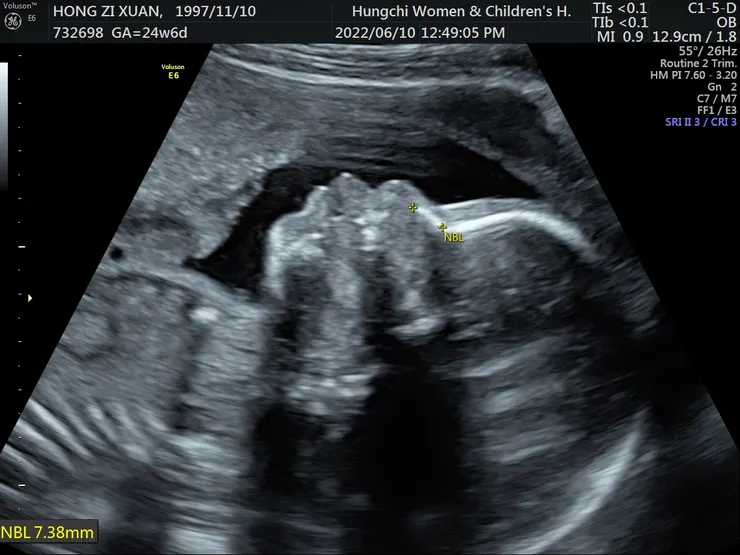

懷孕的過程中,我沒有太多孕婦不適的症狀,只有水腫,還有過程中確診一次!直到生產過程有點艱辛,我在待產室待了兩天兩夜,宮縮規律,羊水也破了,寶寶頭也下來了,可是子宮頸開到兩指半就不開了,所以吃了全餐,後來剖腹了!

在111年9月11日晚上小寶寶出生了,這個禮物也就此來到了這個世上,小寶寶開始適應這個世界,而我也開始了媽媽之路,老天給的這個禮物,真的很珍貴!